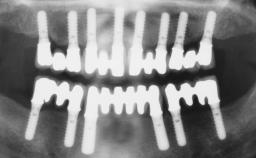

Dr. Gallucci is the Chair of the Department of Restorative and Biomaterial Siences at Harvard School of Dental Medicine. ITI Fellow since 2004, Chair of the ITI Scholarship Center at Harvard.